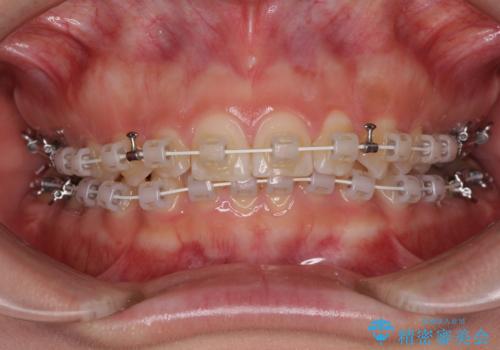

- 審美装置

- 1年3ヶ月

左上の歯列は補助装置により速やかに移動し、1年程度で奥歯の咬み合わせが改善され、1年3ヶ月の短期間でしっかりと仕上げることができました。